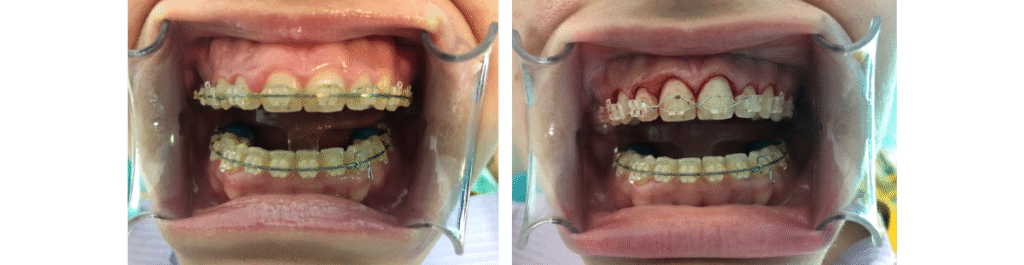

Caso de alargamiento